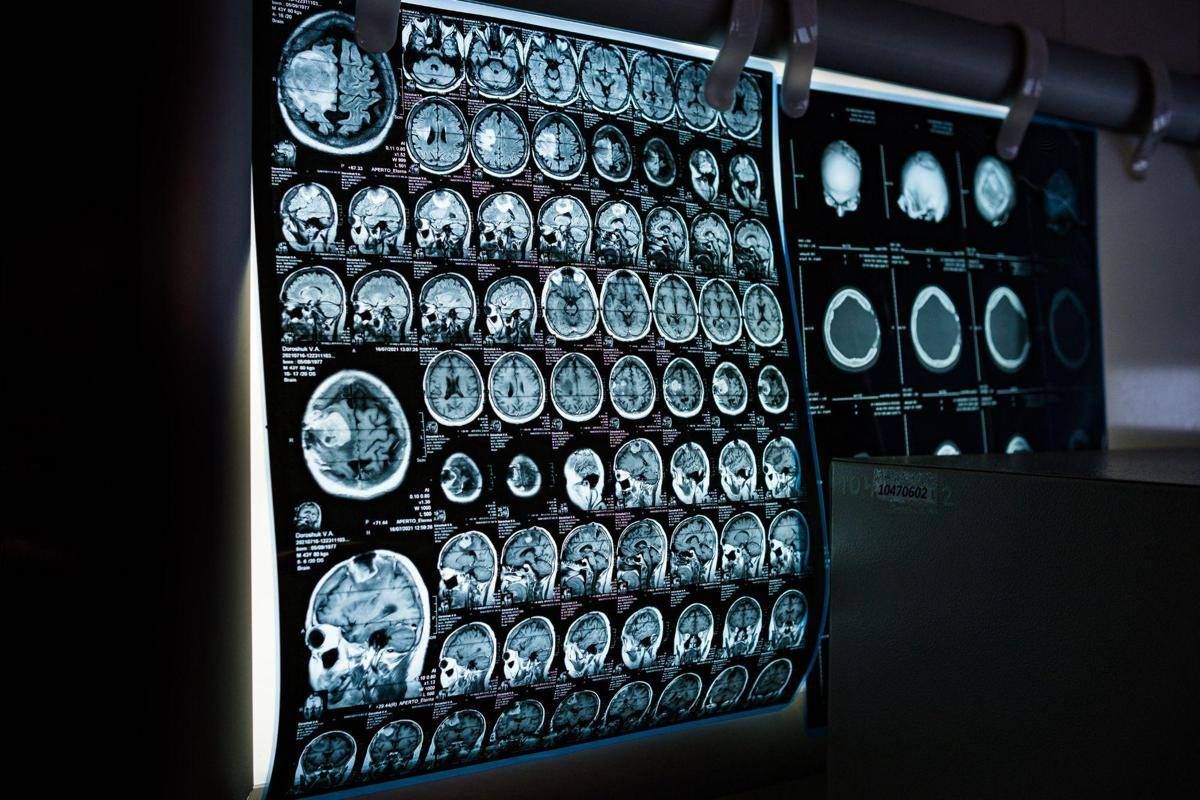

Uno spray nasale testato sui modelli animali potrebbe invertire l’invecchiamento del cervello con sole 2 dosi, riducendo drasticamente l’infiammazione cerebrale, ripristinando le centrali energetiche cellulari del cervello e migliorando così significativamente la memoria. Un processo di ringiovanimento che agirebbe nel giro di poche settimane per durare mesi.

E’ il risultato dello studio condotto dai ricercatori della Texas A&M University (Naresh K. Vashisht College of Medicine) negli Stati Uniti. Lo spray contiene minuscole particelle biologiche note come vescicole extracellulari (Ev), che agiscono come veicoli di consegna con a bordo un potente carico genetico, i microRna. Le sostanze aggirano lo scudo protettivo del cervello e viaggiano direttamente nel tessuto cerebrale, dove vengono assorbite. Arrivati a destinazione nelle cellule immunitarie residenti nel cervello, i microRna ‘spengono’ i sistemi noti per essere responsabili dell’infiammazione cronica nel cervello che invecchia.

Per spiegare il senso di questo processo, gli scienziati invitano a immaginare il cervello come un motore ad alte prestazioni: nel corso dei decenni questo motore non solo si usura, ma inizia anche a surriscaldarsi. Piccoli ‘focolai’ di infiammazione covano nelle profondità del centro della memoria, creando una persistente nebbia mentale (brain fog) che rende più difficile pensare, formare nuovi ricordi o persino adattarsi a nuovi ambienti, aumentando al contempo il rischio di disturbi come il morbo di Alzheimer. Questo processo a lenta combustione viene chiamato neuroinfiammazione. E per decenni si è pensato che fosse il prezzo inevitabile dell’invecchiamento. Ma il nuovo studio, pubblicato sul ‘Journal of Extracellular Vesicles’, suggerisce che l’ondata infiammatoria potrebbe essere reversibile.